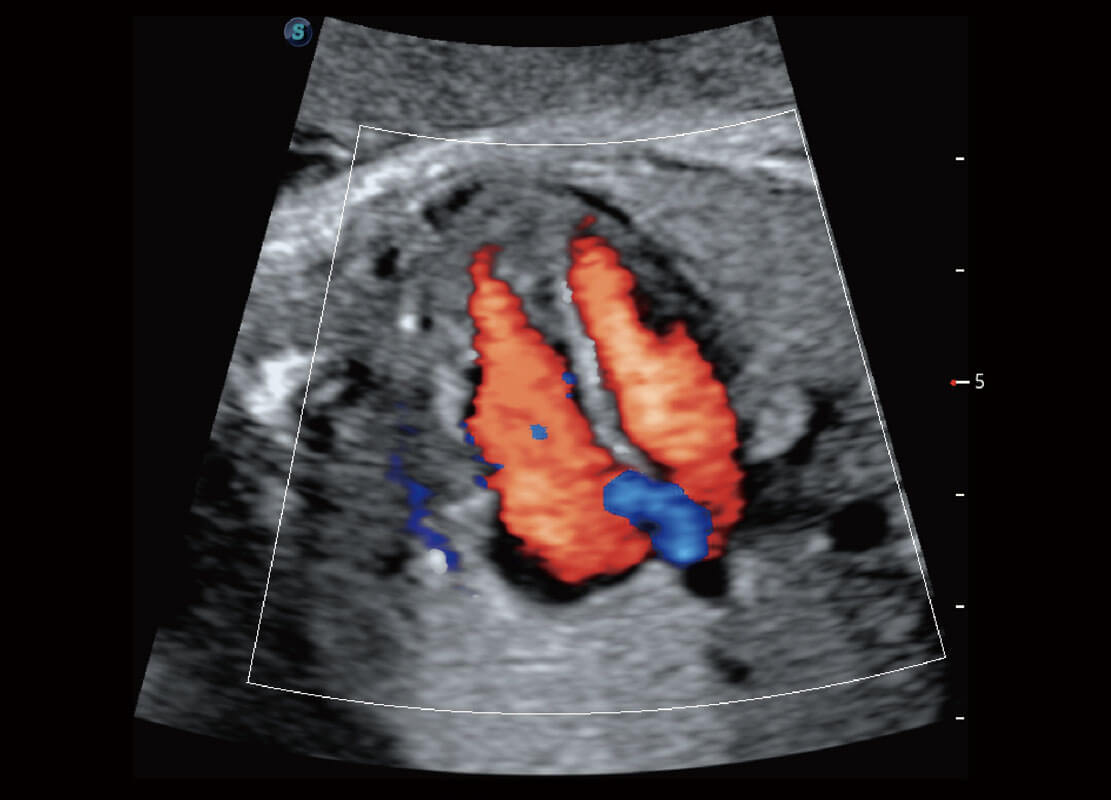

胎心筛查

P60搭载一系列胎儿心脏成像技术,实现精细的胎儿心脏评估。

• 四腔切面

• 四腔心血流

• 右室双出口